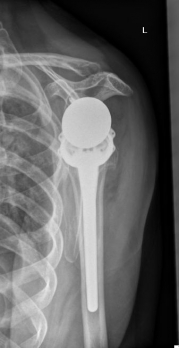

Bilder: Hier wurde ein Oberarmbruch mittels Inverser Schulterprothese bei mehrfragmentärerm Bruch mit Beteiligung der Gelenkfläche versorgt. Hierzu wurde der gebrochene Oberarmkopf entfernt und durch die (Endo-)Prothese ersetzt. Diese ist im Oberarmknochen durch den Prothesenschaft und im ehemaligen Gelenkpfannenbereich mit der sog. Glenosphäre mit Schrauben verankert. Anatomisch bewegt sich der runde Oberarmkopf in einer schalenförmigen Pfanne an der Schulter. Bei der Inversen Prothese werden Kopf und Pfanne miteinander getauscht (vgl. Bild Anatomische Prothese) , wodurch eine verbesserte Funktion bei bereits vorbestehenden Sehnenschäden der Rotatorenmanschette erreicht werden kann.